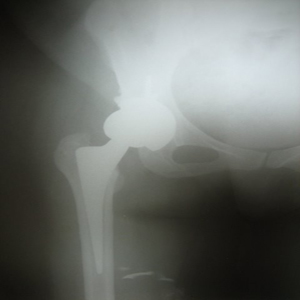

NEW TECHNIQUE FOR HIP ARTHRITIS

30 years old lady presented with complaint of pain right hip since 7 yrs and getting worse since 1 month. She is unable to walk and stand for a long time.

On examination she is having a painful limp, shortening of right lower limb, her hip movements are restricted and painful.

Xray showed evidence of old perthes disease and secondary osteoarthritis of right hip.

In view of her young age , an uncemented Total Hip Replacement was carried out.

Hip Arthritis Uncemented Replacement

Post operative period was uneventful and she is walking painfree from 2nd post operative day .